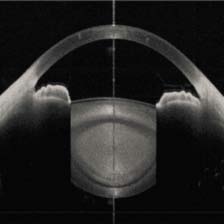

眼前段成像

典型应用 | 眼前段成像、内窥镜、皮肤科、心脏病学、无损检测等等 | 高速视网膜成像 | 生物测量断层扫描 | ||||||